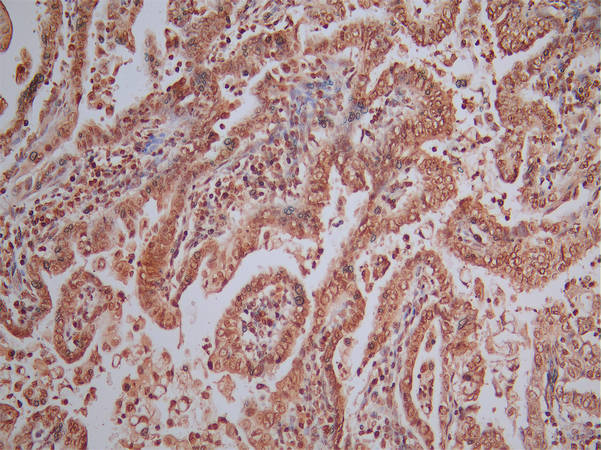

IHC image of CSB-RA001492MA1HU diluted at 1:50 and staining in paraffin-embedded human endometrial cancer performed on a Leica BondTM system. After dewaxing and hydration, antigen retrieval was mediated by high pressure in a citrate buffer (pH 6.0). Section was blocked with 10% normal goat serum 30min at RT. Then primary antibody (1% BSA) was incubated at 4°C overnight. The primary is detected by a Goat anti-Mouse IgG labeled by HRP and visualized using 0.05% DAB.